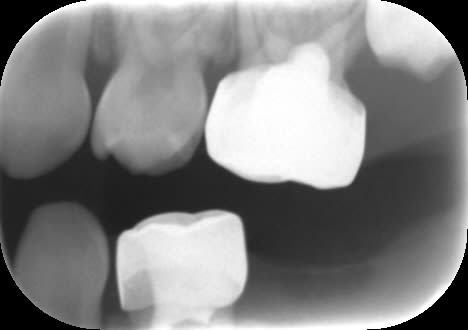

Radios de contrôle.

Pour 65, on voit sur la vue clinique une large canal palatin ovalaire. L'image radiographique correspond probablement à la fusée d'IRM dans l'entrée de ce canal. Je ne pense pas avoir perforé (j'espère !).